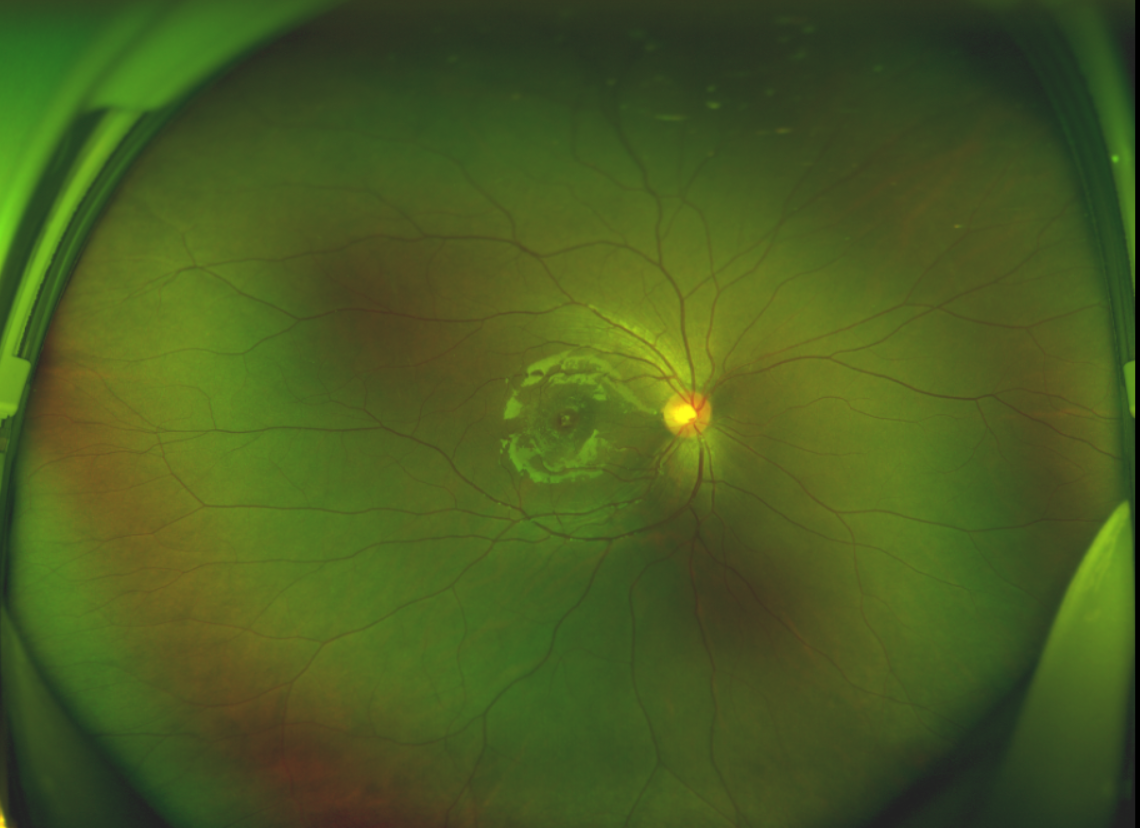

黃斑位于視網(wǎng)膜正中心,是視覺最敏銳的區(qū)域,堪稱“眼底的心臟”,負(fù)責(zé)我們閱讀、駕駛、識(shí)別人臉等精細(xì)視覺。 當(dāng)黃斑區(qū)的神經(jīng)組織出現(xiàn)全層缺損,形成一個(gè)“孔洞”,即為黃斑裂孔,它會(huì)直接導(dǎo)致中心視力急劇下降、視物變形、視野中心出現(xiàn)暗區(qū)。

除此之外,利用自體組織覆蓋為黃斑裂孔提供了理想的愈合環(huán)境,裂孔閉合速度顯著快于傳統(tǒng)方法。誠誠接受手術(shù)24小時(shí)后,檢查可見內(nèi)界膜瓣位置良好;術(shù)后1個(gè)月,黃斑裂孔已經(jīng)閉合,視力恢復(fù)到0.5;術(shù)后兩個(gè)月,視力進(jìn)一步提升到0.7。